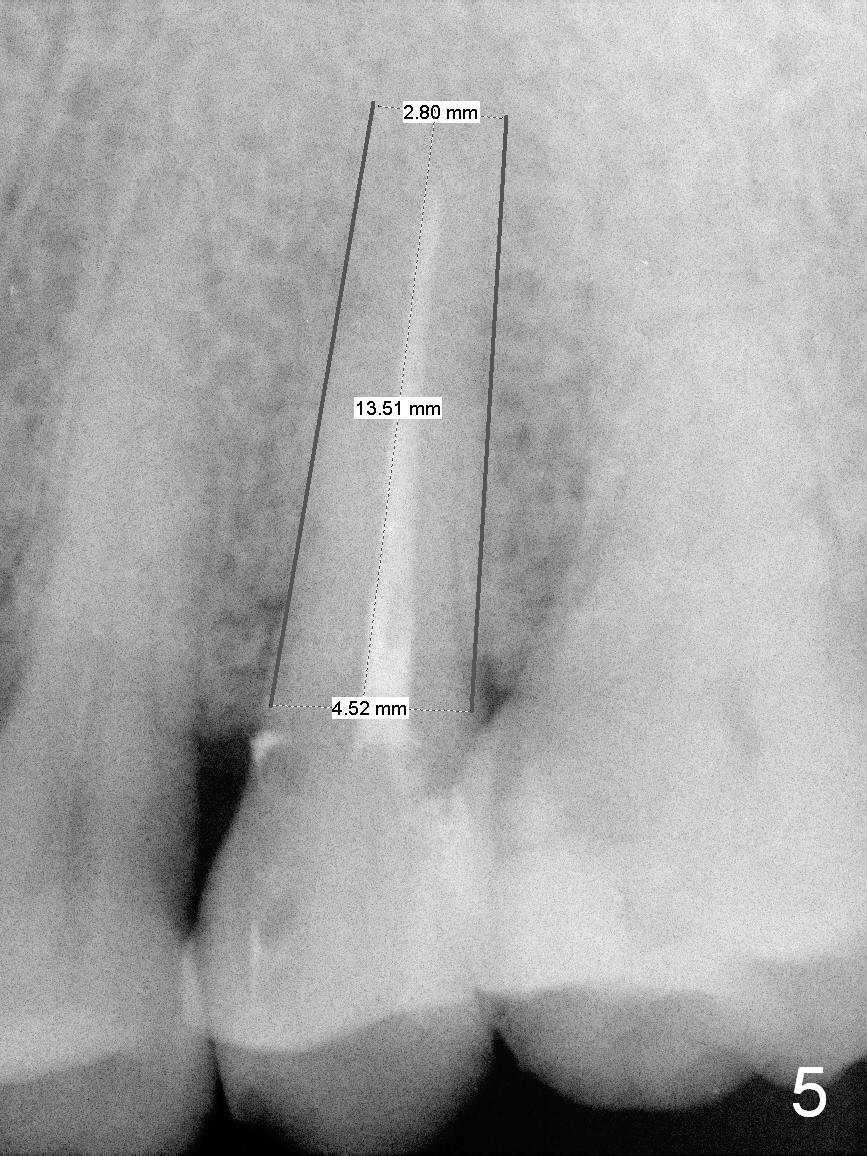

A 48-year-old man (CM) finished root canal therapy for the tooth #13 2.5 years ago (Fig.1). The tooth fractured lately (Fig.2). In spite of the fact that there is no periapical radiolucency in the most recent PA (Fig.3), the socket will be treated with No Antibiotic. Osteotomy is initiated at the junction of the lower and middle thirds of the palatal wall. The palatal cusp subgingival fracture may cause bone resorption in the palatal wall (at the crest). A 14 (Fig.4) or 13.5 (Fig.5) mm bone-level implant is probably going to have 8 mm contact with new bone.